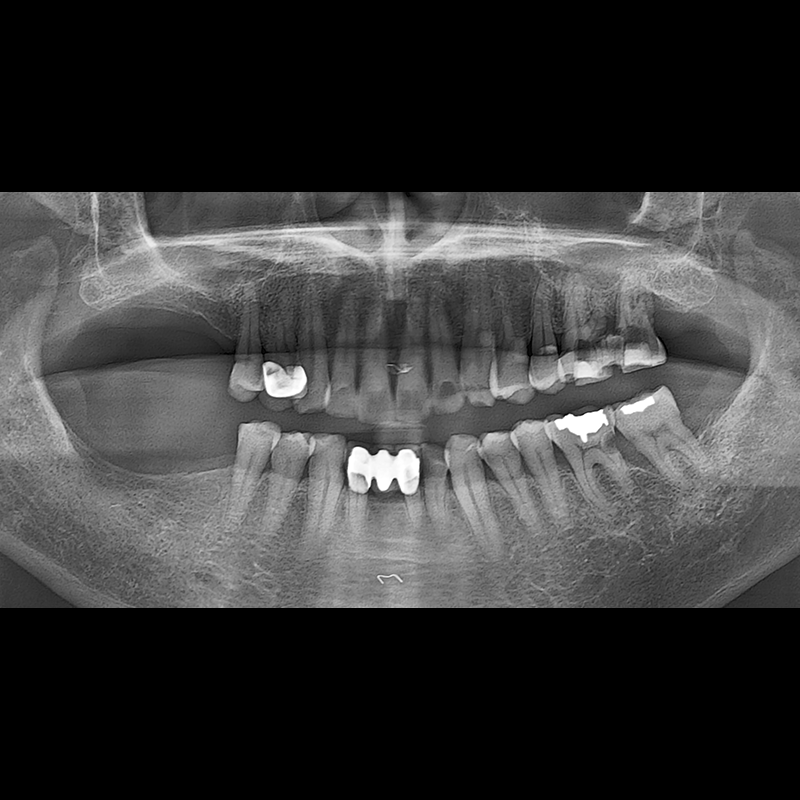

インプラント手術事例 2025.05.30

欠損した歯の部分と、生かしにくい歯の位置にインプラントを植立しました。